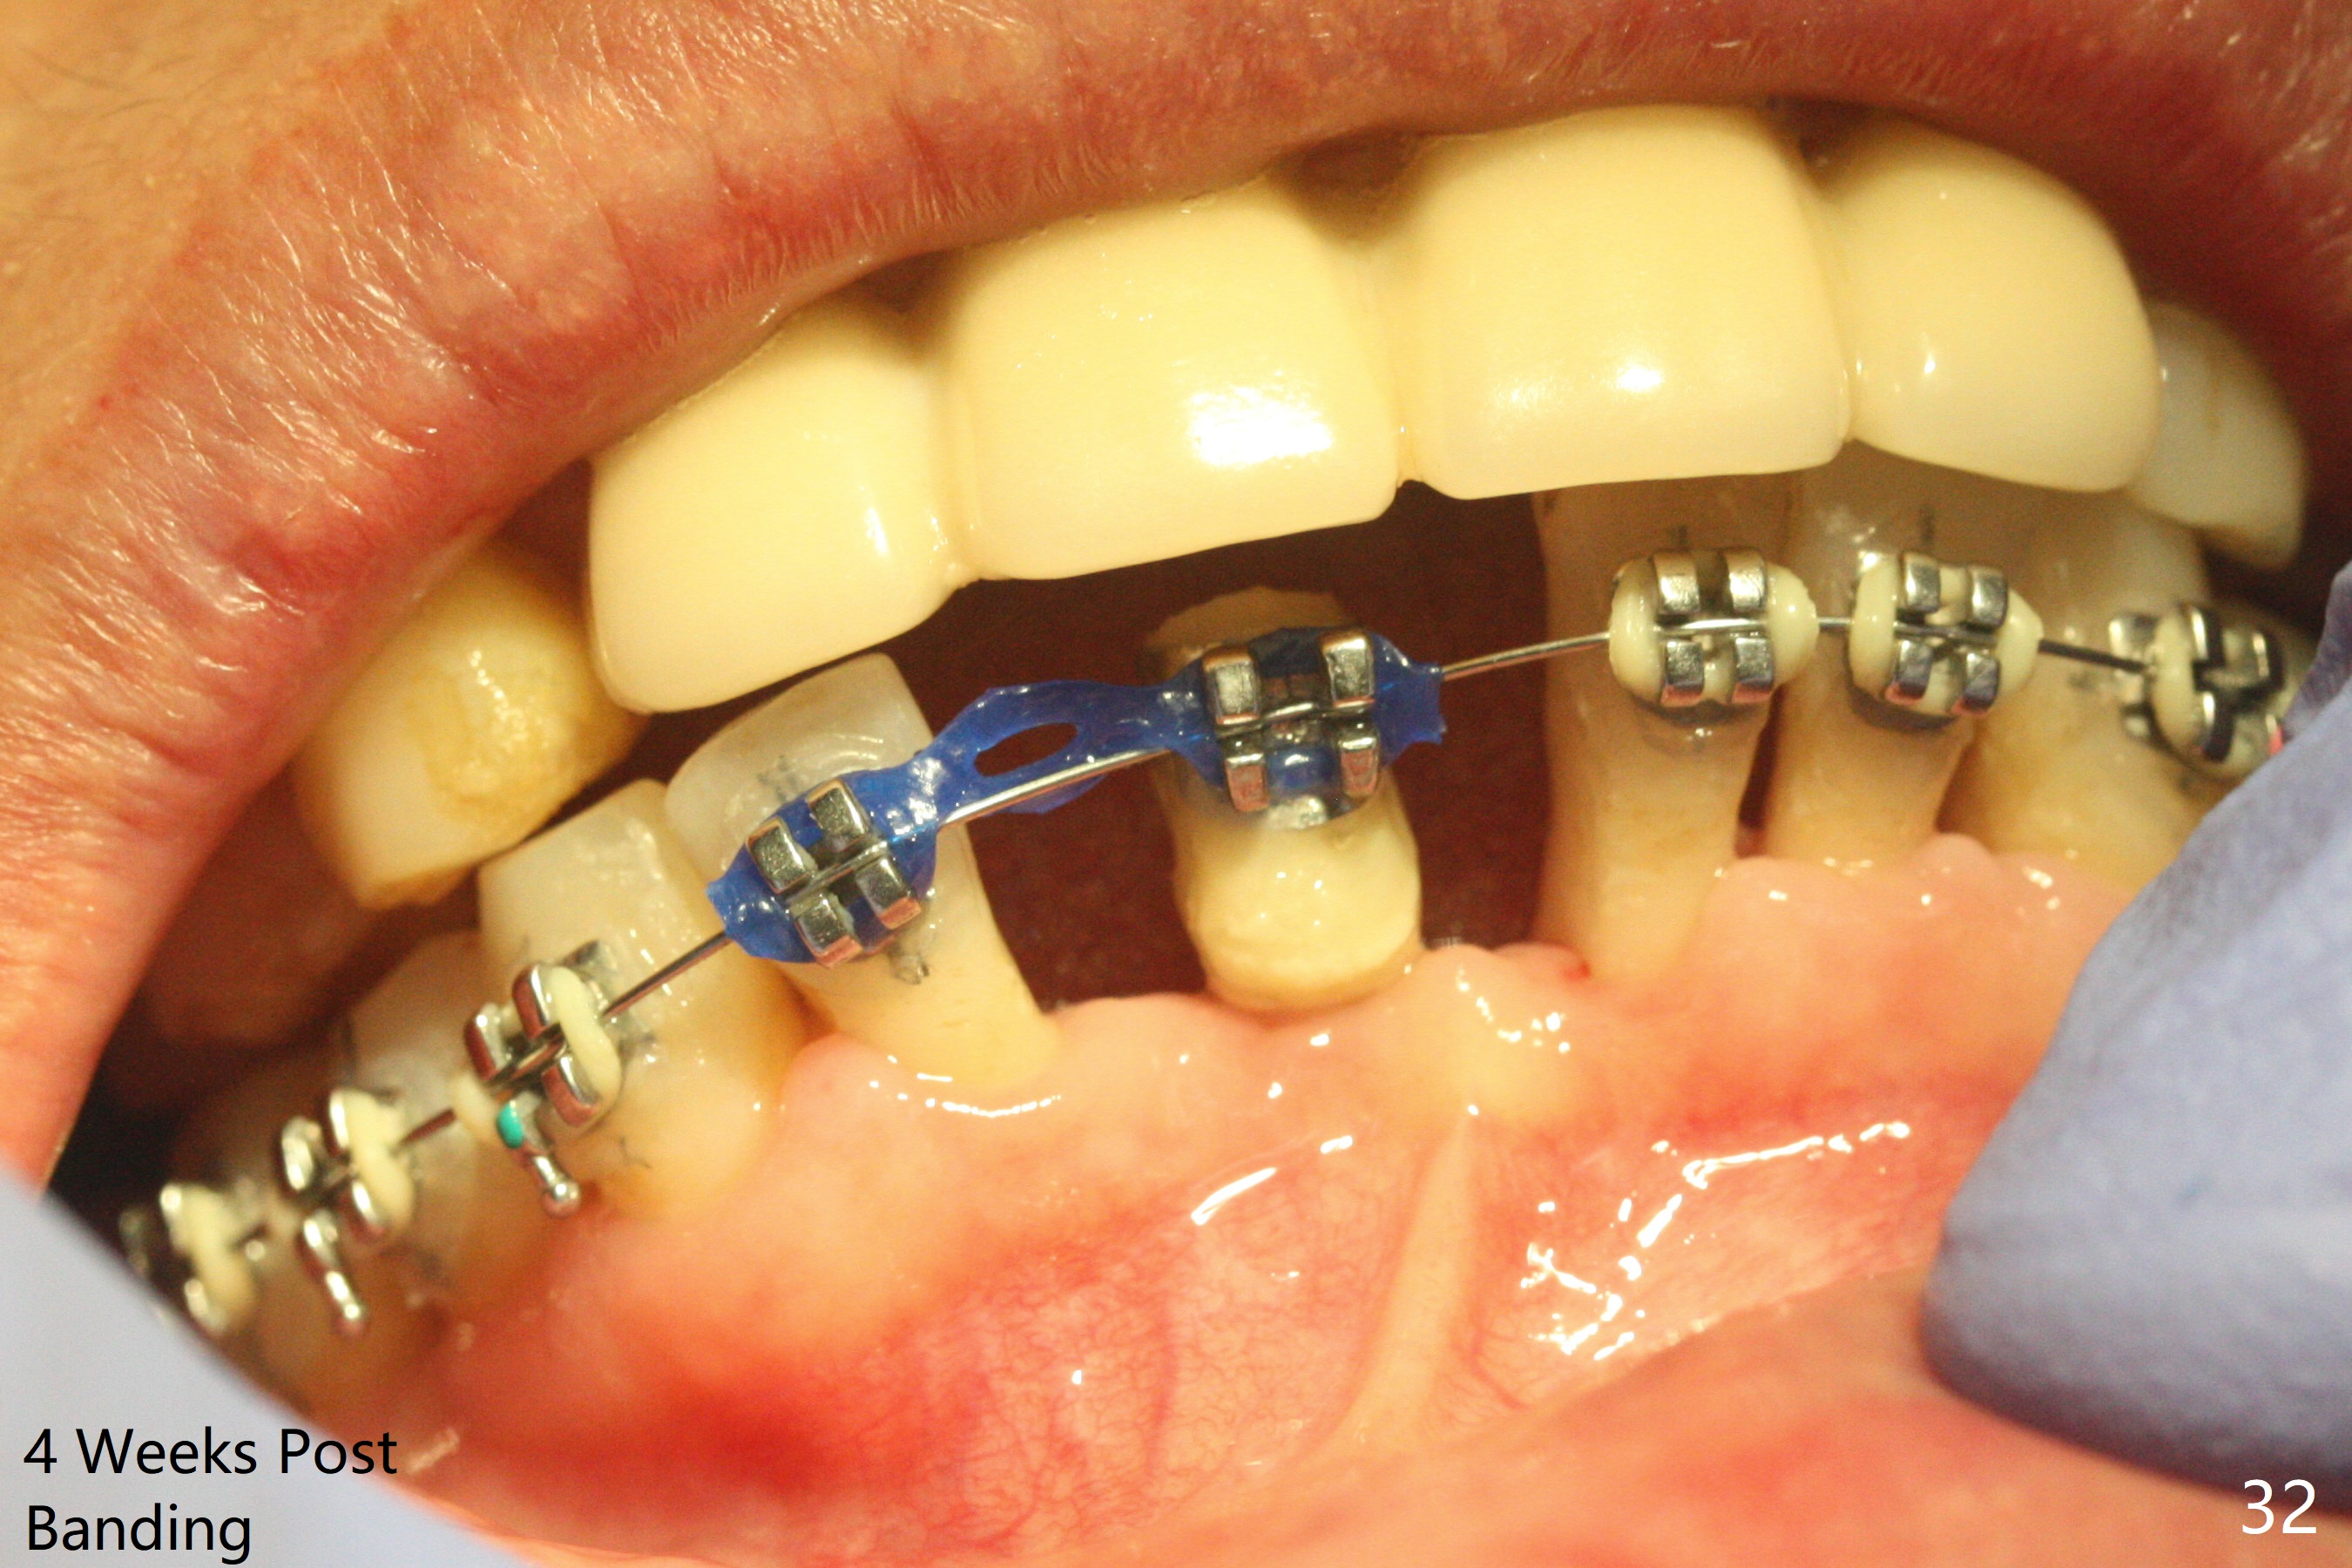

56岁女十分恐惧治疗,缺失右下1,其余切牙由于骨质吸收颊侧移位(图一:1,2),但是她不愿意拔除,同意右下1种植,牙周骨手术,植骨;植体整合后作为支抗,矫正移位下门牙。为了防止忘记舌侧瓣分离,先做舌侧切口(图二),然后颊侧瓣松弛分离(图三),包括使用前牙隧道刀(图四)切断颊侧骨膜,松弛到颊侧瓣能向舌侧牵拉3-4毫米(图五),舌侧瓣骨膜下广泛,深部分离(好像不能切断骨膜,图六),放置导板,磨平狭窄的牙槽嵴(图七:O(osteotomy)),植入2.5x12(4)毫米一段式植体(图八:故意舌侧植入,以便以后矫正),在颊侧骨板打多个出血洞(图八:箭头),然后把在平的器皿上形成的粘性骨板(sticky bone,图九),放置于植体和移位切牙周围(图十),接着使用消毒过的橡皮障punch(图十一(纸头相当于PRF膜;事先给助手示范))在三个PRF膜(图十二)打洞,套在植体和门牙上(图十三: 箭头),防止膜(图十四)和骨块(图十五,十六:*)移位,最后还必须使用最原始方法牙周敷料保护伤口(图十七)。术后9天,舌侧牙周敷料脱落,伤口稍微裂开(图十八)。术后18天撤除敷料,伤口裂开处有新鲜肉芽组织生长(图十九(*:下面是填入的骨粉,将是增宽的牙槽嵴(如果你是乐观主义者)),二十)。病人十分感激我们帮助她度过难关。她的确有sleep apnea,否定tongue thrust。术后三个月植体周围没有明显骨质吸收(图二十一至二十三),左下1,2轻度反合(图二十四),植体周围软组织健康(图二十五),5-5安置矫正器(图二十六,二十七,12 niti)。一周后下切牙向舌侧移动(图二十八),左下1,2反合纠正(图二十九)。再一周变化不大(图三十),植牙圈有些松动,两周后将重做临时牙冠,槽往舌侧移动。结果病人提前回来,植牙槽舌侧移位。一周后右下2不适(图三十一),尝试近中牵引(图三十二)。